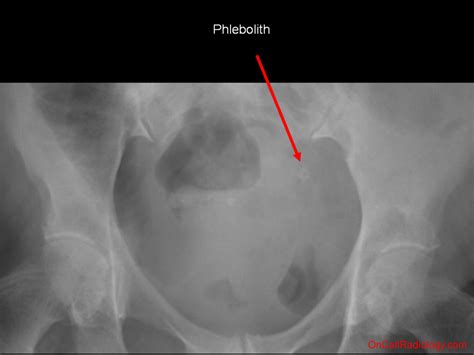

Phleboliths are small, calcified deposits that form within veins. They are typically composed of calcium and other minerals and can vary in size from a few millimeters to several centimeters. These deposits are often incidental findings during imaging studies, such as X-rays, CT scans, or MRIs. While phleboliths can occur in various parts of the body, their presence in the pelvis is particularly noteworthy due to the anatomical complexity of the region.

Detecting phleboliths in the pelvis typically involves imaging techniques that can visualize the calcified deposits. The most common diagnostic methods include:

• X-Rays: Plain radiographs can sometimes detect phleboliths, especially if they are large enough. However, X-rays are less sensitive compared to other imaging modalities.

• Computed Tomography (CT) Scans: CT scans provide detailed images of the pelvic region and are highly effective in identifying phleboliths. They offer a three-dimensional view of the area, making it easier to locate and assess the deposits.